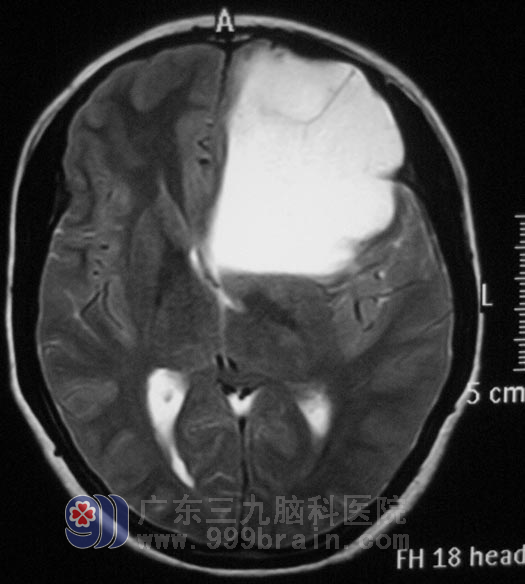

次日,卢女士在先生的陪伴下来到广东三九脑科医院,头颅MR检查,结果提示:左侧额颞叶大片异常信号影,大小约7.2cm×6.0cm×5.4cm,头颅MRS及弥散检查进一步考虑为低级别胶质瘤。鉴于卢女士的病程短、症状发展快,综合神经外科 鲁明主任指示抓紧时间完善各项术前准备。2月27日,在全麻下行左侧额叶肿瘤切除术,术中使用导航仪定位,显微镜下见左额叶局部脑组织呈灰白色色泽改变,根据术前讨论计划,术中唤醒麻醉,在患者语言配合及肢体运动情况下使用超声吸引切除肿瘤,术中对语言及肢体运动保护完好。术后卢女士未出现偏瘫、失语等手术并发症。经病理证实为:原浆性星形细胞瘤(胶质细胞瘤I-II级)。

▲手术前